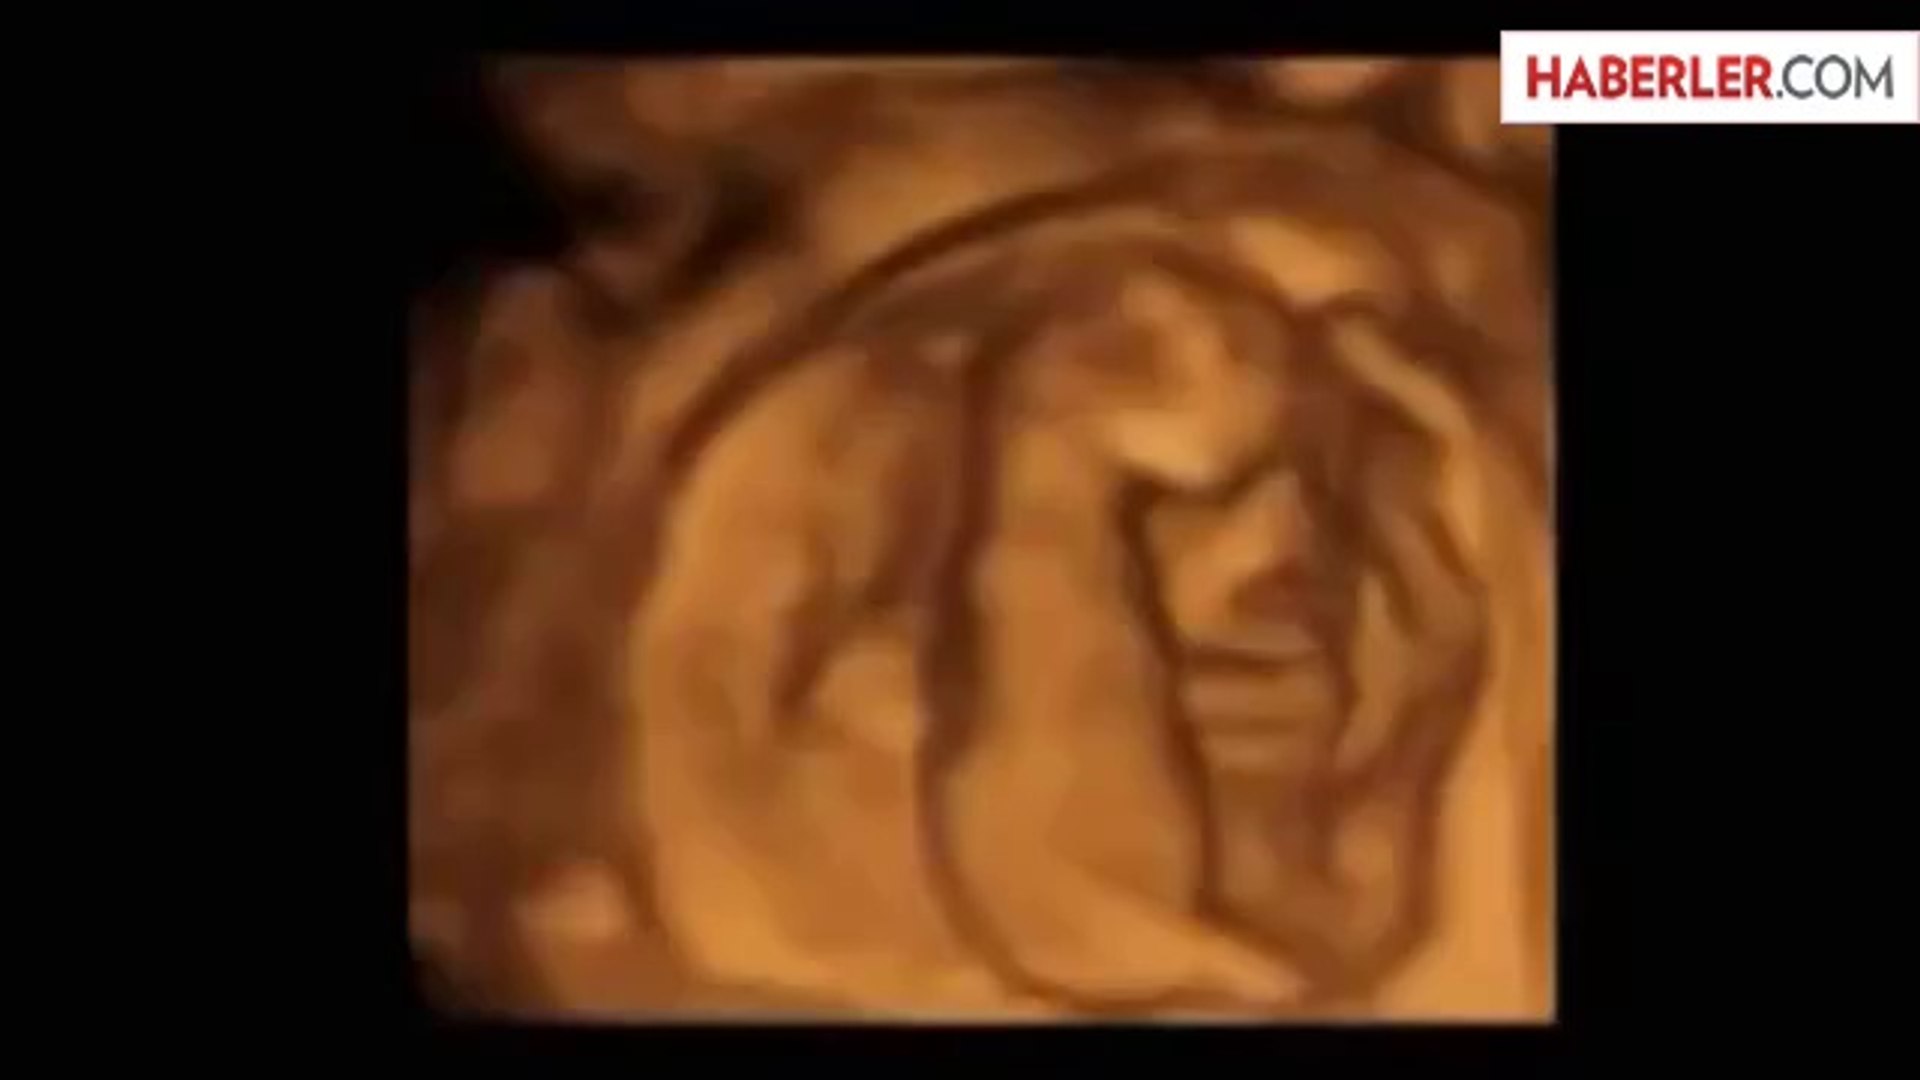

anne karnindaki kedilerin inanilmaz goruntusu